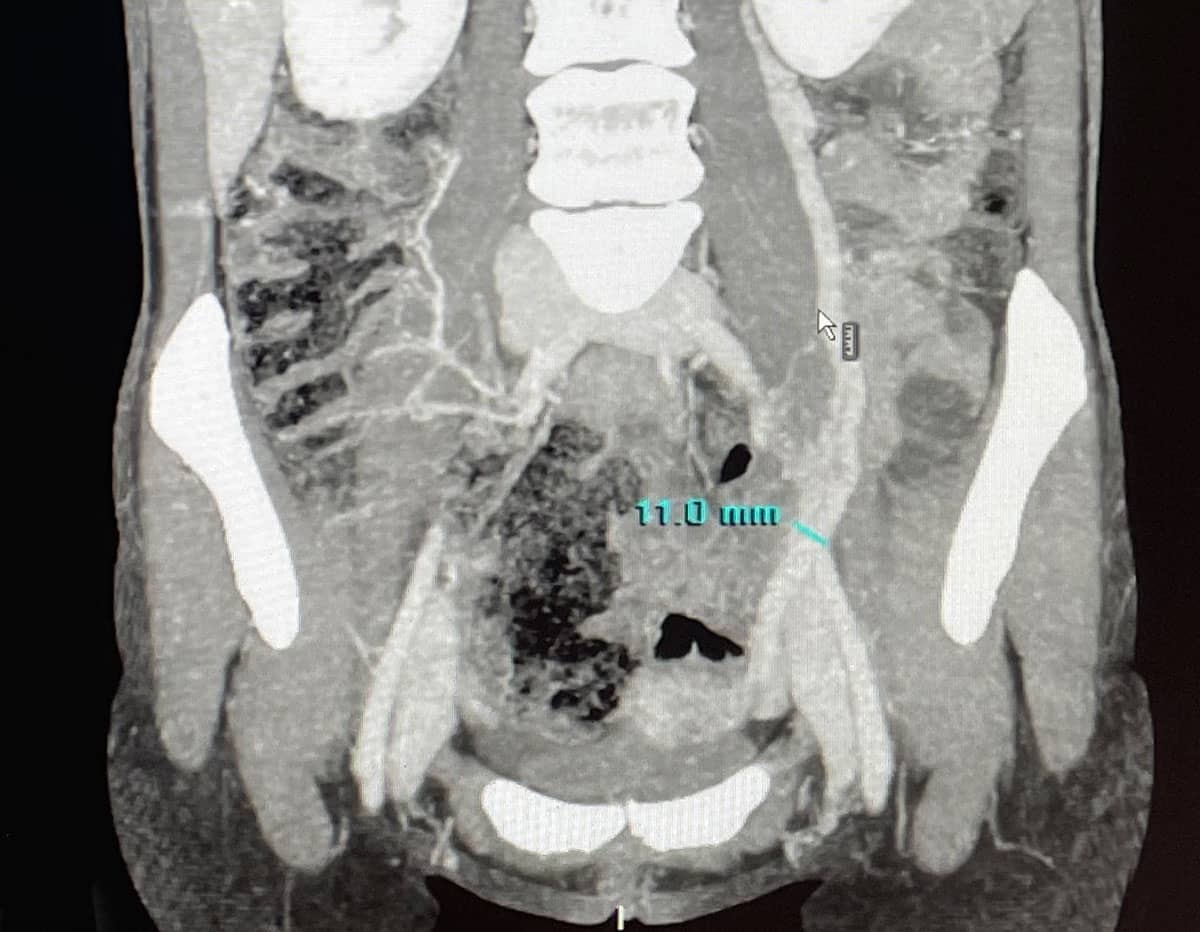

Como siempre es fundamental hablar con el paciente para que nos cuente sus síntomas. Realizamos también una exploración física para ver si existen varices en piernas o varices vulvares. Además, un examen ginecológico por parte del especialista también es fundamental para valorar otras causas de las molestias del paciente. A continuación, nuestra prueba de imagen inicial y fundamental es el eco-doppler abdominal o transvaginal y de miembros inferiores. Una vez confirmado o con una alta sospecha se puede completar el diagnóstico con un angioTc o una Resonancia Magnética para descartar otras causas y valorar la anatomía.

En último lugar, el diagnóstico de confirmación nos lo da la flebografía que generalmente se realiza en el mismo acto en que se tratan.